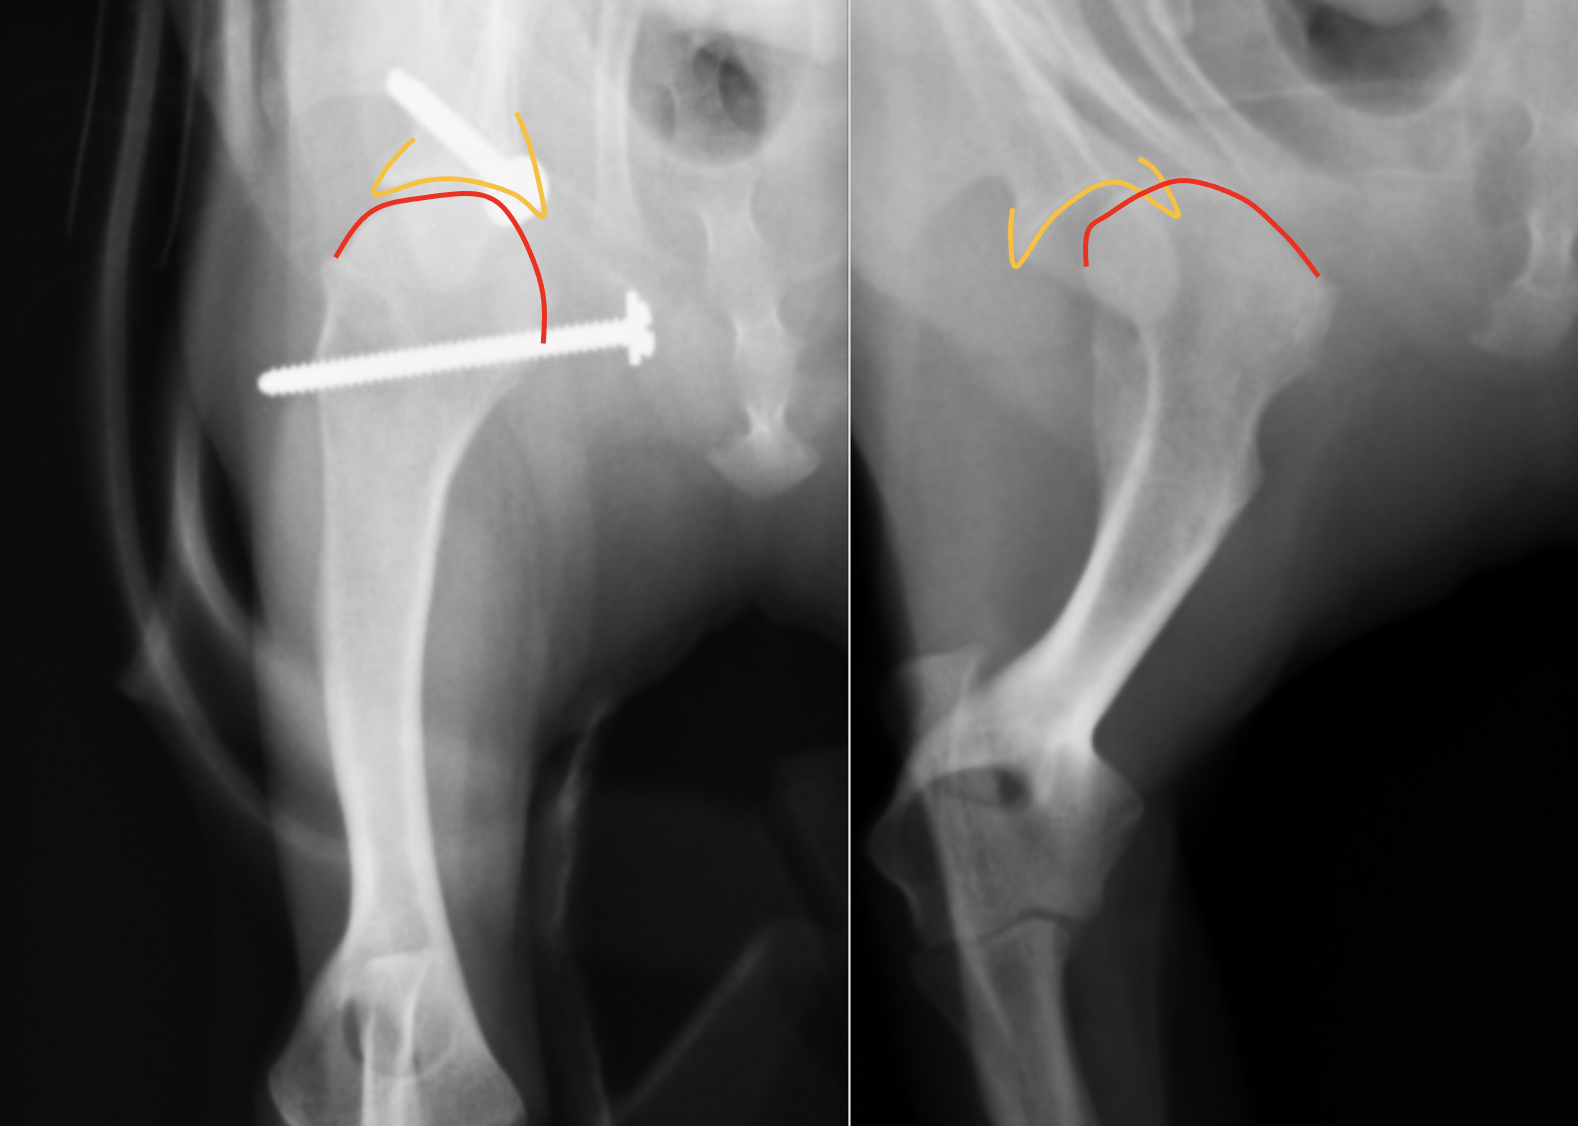

横から見たレントゲンです。右が術前、左が術後です。こちらも線を引くと

右のレントゲンではオレンジと赤のラインが全く合っていなかったのが、左の術後ではピッタリとあっているのがわかると思います。